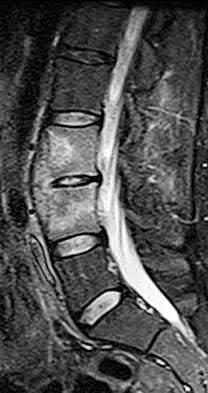

Figures 9a through 9c are the MRI scans of a 65-year-old woman on dialysis who has thoracic back pain, malaise, and an elevated erythrocyte sedimentation rate (ESR). The clinical history and imaging findings are most consistent with

Corrent answer: 3

The sagittal MRI scans are pathognomonic for diskitis and osteomyelitis with fluid signal and destructive changes in the disk on T2 (Figure 9a), low signal with blurring of the disk margins on T1 (Figure 9b), and on the T1 gadolinium image (Figure 9c) vertebral body enhancement on either side of the affected disk with dark signals within the disk corresponding to the bright fluid signal from the T2 image. Metastatic carcinoma tends to affect the vertebral body with relative disk sparing, and lymphoma can affect the vertebral body but often has soft tissue extending within the spinal canal. Osteoporotic fractures are contained with the vertebral body. Renal osteodystrophy can result in a diskitis picture with disk destruction but one would not expect an elevated ESR or malaise, and this is much rarer than diskitis in dialysis patients.